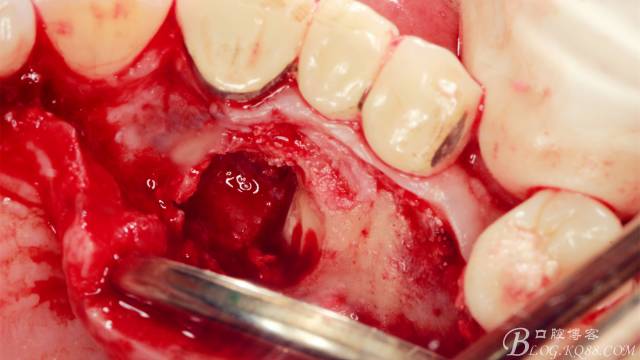

長柄裂鉆分離牙冠,微創(chuàng)挺插入后順時針或者逆時針輕擰一下,手上去感受牙冠斷開的那一瞬間,有時候耳朵也能聽見啪得一聲,不過此刻因為牙冠周圍的骨阻力,牙冠是不能取出的。

T形分牙,把牙冠分為兩瓣,減少阻力。

分別挺出兩瓣牙冠,可見牙根截斷面。